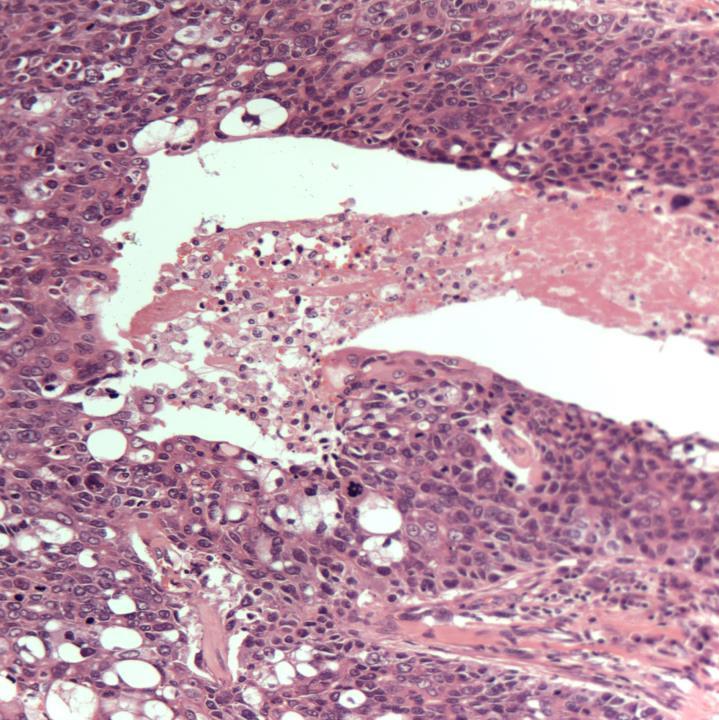

Case 19

◼ Fibroepithelial lesion

◼ Stromal overgrowth

◼ Stromal cellularity

◼ Leaf-like pattern

◼ Stromal atypia

◼ Infiltrative margin

◼ Phyllodes tumour (borderline)

◼ Cellular fibroepithelial lesion and benign phyllodes are managed similarly.

◼ Borderline and malignant phyllodes: excision with margin.

DD: Spindle cell lesion on core biopsy

◼ Look for biphasic pattern

◼ Look for DCIS

◼ A panel of cytokeratins (including basal cytokeratins) to exclude metaplastic carcinoma